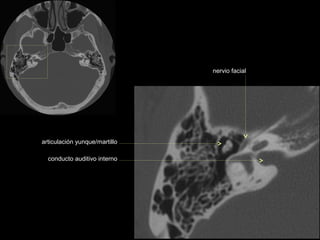

articulación yunque/martillo

conducto auditivo interno